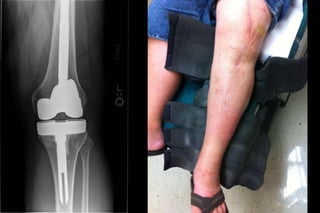

68 yo male

6 weeks postop